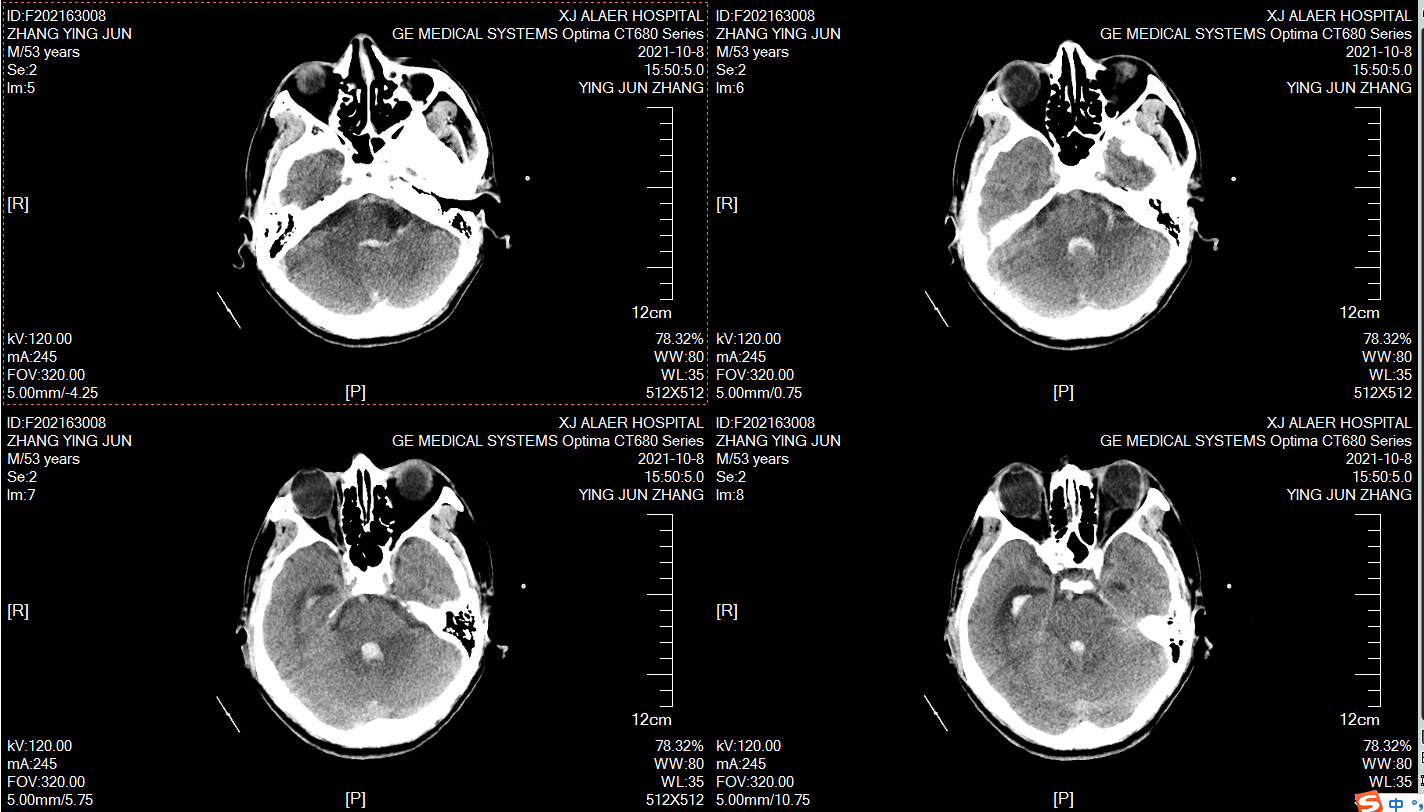

术前颅脑CT,男性,59岁,突发意识不清2小时,目前昏迷,GCS6分,右侧瞳孔4mm,左侧瞳孔2mm,脑室出血,烟雾病!